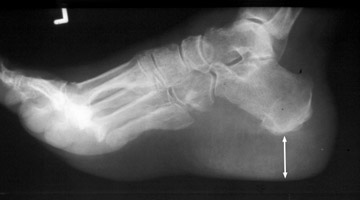

Diagnosis:Acromegaly Discussion:Single lateral radiograph of the foot with a grossly enlarged and thickened calcaneal heel pad. Although not pathognomonic, a heel pad thickness greater than 23 mm may indicate acromegaly. The overabundance of growth hormone in acromegaly causes, among other things, gradual enlargement of hands, feet, and exaggeration of facial features. Not limited to the bones, however, enlargement of other parts of the body, such as the soft tissues of the heel may help to diagnose acromegaly. References: